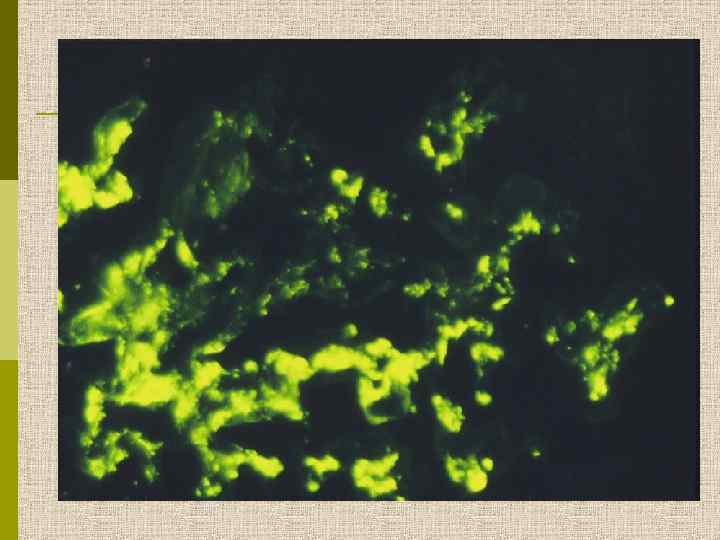

Мезангиопролиферативный гломерулонефрит (депозиты Ig. А в мезангии)

Мезангиопролиферативный гломерулонефрит (депозиты C 3 в мезангии)

Морфология Ig. А-нефропатии q Определяющий симптом – диффузные отложения Ig. A в мезангии, коррелирующие с электронноплотными депозитами в мезангии при электронной микроскопии q Могут наблюдаться депозиты С 3, Ig. G, реже Ig. M, а также Ig. A в капиллярной стенке q При световой микроскопии – от минимальных изменений до сегментарной или диффузной мезангиальной гиперцеллюлярности, с развитием фокального сегментарного склероза, атрофии канальцев и интерстициального фиброза q При электронной микроскопии – высокая частота фокального истончения ГБМ